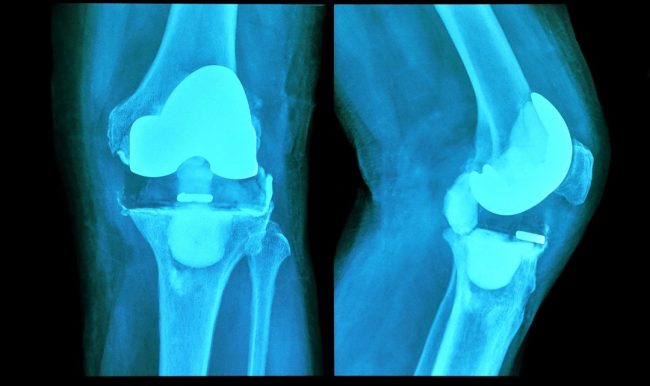

Wszystko, co należy wiedzieć o protezach stawu kolanowego

Wymiana stawu kolanowego polega na zastąpieniu go częścią syntetyczną w drodze zabiegu chirurgicznego. Jest to implant, który jest umieszczany w uszkodzonej strukturze i zastępuje jej funkcję, umożliwiając pacjentowi ponowne poruszanie stawem i eliminując ewentualne dolegliwości bólowe. Najczęstszą przyczyną wstawienia protezy jest choroba zwyrodnieniowa stawu kolanowego, która powoduje uszkodzenie stawu. Ale także w przypadku złamań, w…